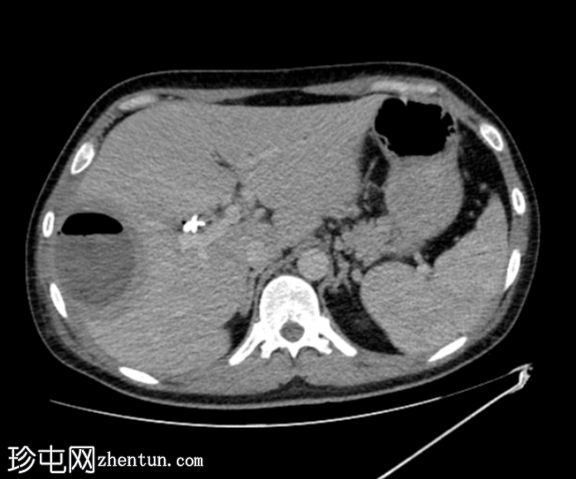

轴位增强扫描

3.png

动脉期

增强扫描图像显示囊肿边缘强化,周围可见晕环,呈双靶征。

该患者近期行胆囊切除术及胆总管支架置入术,近期主诉右上腹疼痛及发热。影像学表现符合医源性化脓性肝脓肿介入治疗后的典型特征,右肝叶囊性病变可见管腔内气体和气液平面,增强扫描后边缘强化,并可见经典的双靶征。患者接受了超声引导下经皮穿刺引流术治疗。遗憾的是,培养结果尚未公布。

“双靶征”表现为:中央低密度病灶(充满液体)周围环绕着高密度内环和低密度外环。